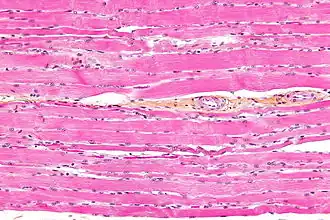

Striated muscle tissue is a muscle tissue that features repeating functional units called sarcomeres. Under the microscope, sarcomeres are visible along muscle fibers, giving a striated appearance to the tissue. The two types of striated muscle are skeletal muscle and cardiac muscle.